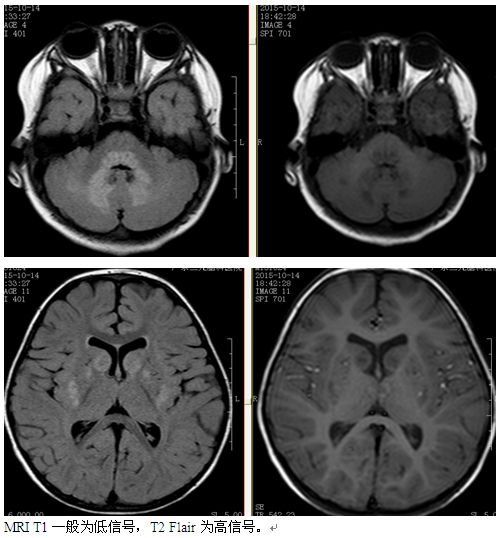

NC脑神经回路调控技术:以神经回路学说为理论基础,从神经回路层面着眼,首次实现扫瞄式检测 同时检测多达300条脑神经回路,密集化鉴别脑神经回路中神经介质紊乱种类与程度,靶向修复并调节神经介质平衡,促进神经元再生修复,重建神经元与神经元之间信息正常传导生理机制,恢复神经回路信息传导畅通。